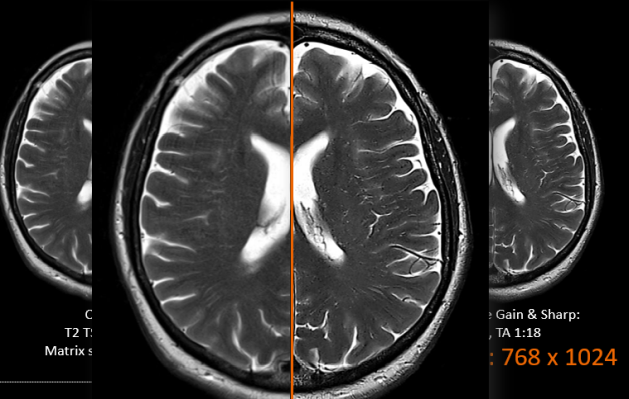

パラレルイメージング、同時多断面励起法、圧縮センシングという3種類の高速撮像法を装備し、微妙なコントラストを維持しつつ、非常に大きな高速化が可能となります。MR検査における患者さまの拘束時間の短縮と効率化を両立させる技術です。

人工知能による画像処理によりノイズ低減と超解像処理が可能になります。これにより検査時間の短縮と高分解能化が行え、患者さまの負担低減と3T-MRIとの併用運用する際の検査枠の偏りの解消が期待できます。